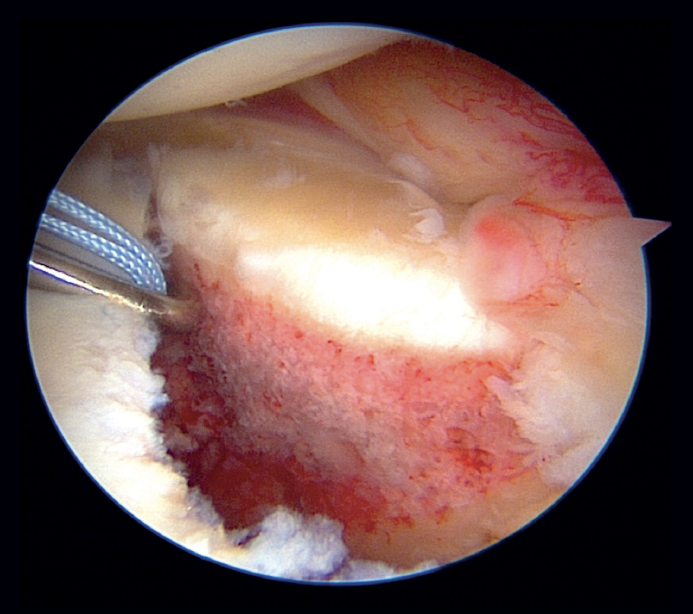

In the modified double-row/double pulley technique, and in addition to the measures commented above, an anchoring was added between the first implant and the second, at the height of half of the fractured bone fragment but in a position medial with respect to the chondral margin of the glenoid cavity (Figure 5). In this case, both the extremities crossed through the capsule at the level of half of the fragment and anterior to the latter at different points, followed by knotting and maintaining reduction of the bone fragment (Figure 6). One of the extremities of the suture knot made was tied to one of the extremities of the lower anchoring, while the other was tied to one of the extremities of the upper anchoring, thereby completing the repair procedure (Figure 7).